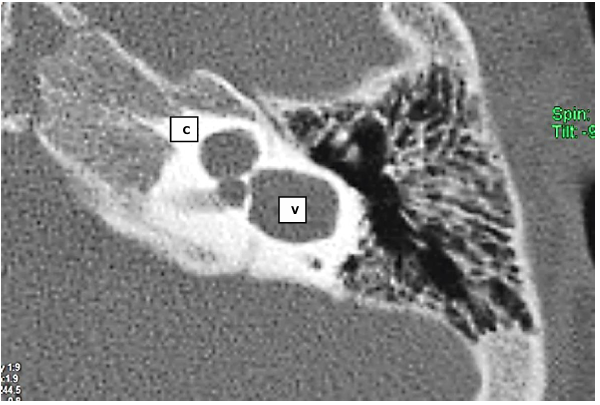

Paciente do sexo masculino, 2 anos, é encaminhado ao serviço de Otorrinolaringologia

devido a atraso de fala e linguagem. Considerando a seguinte sequência de tomografia contrastada,

é correto afirmar que: